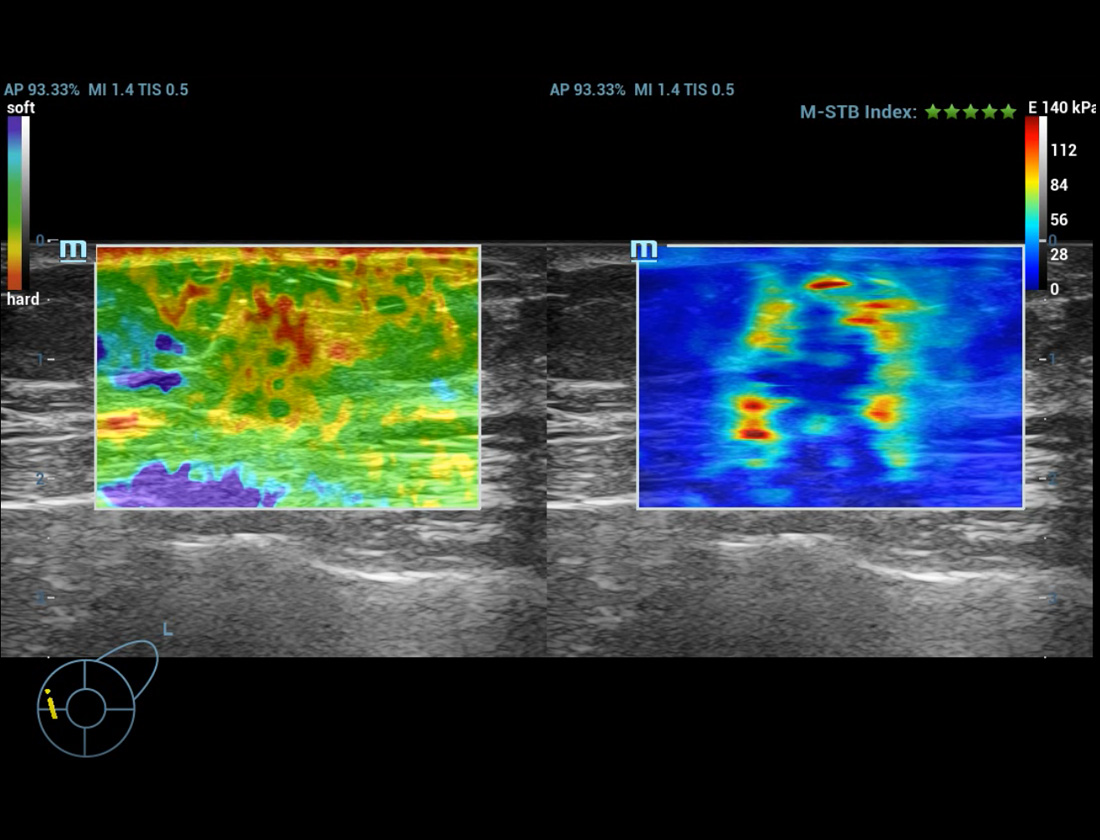

M-Ref. E Compare

M-Ref. E Compare ã Tumor maligno de mama

M-Ref. E Compare oferece suporte û exibi??o tanto da elastografia por deforma??o em tempo real quanto da STE em um û¤nico plano para avalia??o da rigidez do tecido.

Elastografia de deforma??o

- Alta sensibilidade, produtividade, penetra??o e precis?o

- ãInvû°lucroã exclusivo para anûÀlise da ûÀrea de infiltra??o do tumor

Elastografia de deforma??o

E Compare ã Massa mamûÀria no L15-3WU